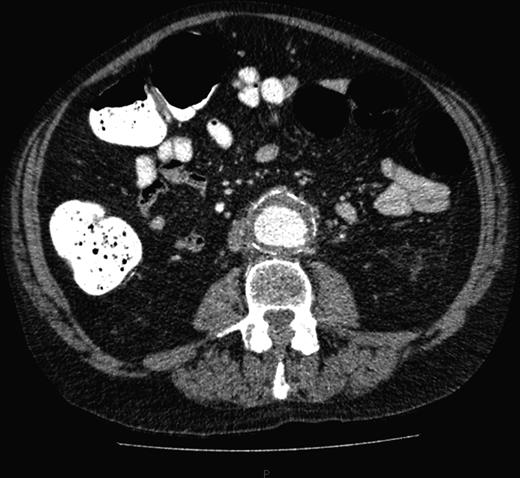

A computed tomography (CT) of the abdomen and pelvis was performed. This showed a grossly distended urinary bladder and compression of the sigmoid colon against the sacral promontory causing bowel obstruction (Figs 1 and 2, respectively) as well as a 4.9 cm abdominal aortic aneurysm without any signs of a rupture (Fig. 3). The plan was to consult our vascular colleagues regarding management of the AAA once the obstruction had settled.

Further image of the same CT scan showing compression of the sigmoid colon against the sacral promontory (see arrow) behind the distended bladder.